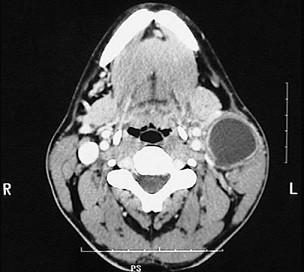

4.圖示是鰓裂囊腫患者的CT 檢查結果,關于此病的描述錯誤的是  (    )

正確答案:D